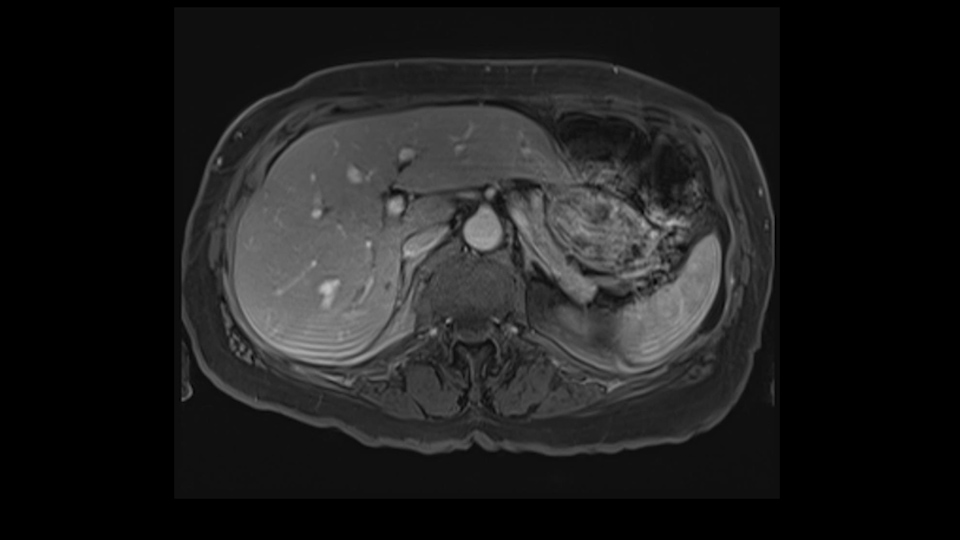

She underwent neo-adjuvant chemotherapy and then had a series of additional investigations and the one that I’m focusing on in more finer detail is an MRI with Primovist and I’ve had the benefit of looking at the report. The main issues are in Segments 5,6, and 7. Three small metastases that remain and the radiologist also comments on the lack of biliary dilatation which was present before; implying that the intrabiliary metastasis somewhere at the origin of the Segment 7 duct, has regressed or been adequately well treated with chemotherapy. That’s probably where the difficult decision making comes in the OR. So from an oncologic point of view, I would plan for a right hepatic lobectomy. The rationale would be that this would include the more peripheral Segment 5, 6, 7 metastases that are obvious but also would take care of the presumed Segment 7 intrabiliary metastasis that does not actually visualize on any of the scans but is assumed to be there with evidence of the duct dilatation which then resolved. One could argue whether we should preserve liver and ignore that duct dilatation that was there before but I think my own preference would be to resect the right lobe and that would certainly include any residual disease in that Segment 7 bile duct and moreover, coming back to do a completion right hepatic lobectomy would be difficult particularly around the porta where this metastasis is presumably still there and even if its quite small.

So when doing a major liver resection, obviously we would focus on a few issues. The first is hepatic parenchyma: is there adequate liver, residual liver and orientation and ratio of the right to left lobe here is pretty normal. It looks like its about 60:40 or 70:30, and because its only a right lobe, I probably wouldn’t do any volumes assuming she has normal liver function which I think she does. The only additional feature of interest is that she has received chemotherapy and one can see the effect of chemotherapy on the density of the liver but again, it doesn’t usually cause significant problems with a short course of neoadjuvant chemotherapy, or liver failure.

So now we’ve assessed extent of metastatic disease, we’ve got some idea of fitness. The last item and I put it third because it’s actually the easiest of the three is what is the extent of the disease within the liver. For that we use contrast-enhanced magnetic resonance scanning, contrast-enhanced MR good for planning treatment.

So look at the MR from two points of view, firstly distribution of the lesions, secondly what kind of parenchyma would need to be resected to remove that disease and what kind of operation would we plan. And again so what we’re planning here would probably be a right hepatectomy. We know that there is plenty of disease-free left lobe. Segment 4 looks nice and clear. So a transection line coming down to about that kind of area would clear all of the disease. So that’s the kind of preoperative planning that we’d need to do.